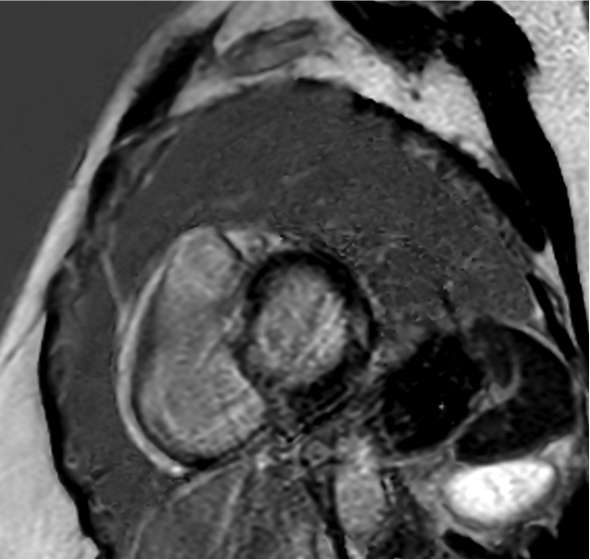

El resultado de la coronariografía fue: arterias coronarias sin lesiones. Depresión moderada-grave de la FEVI por extensa discinesia de los segmentos medio-apicales. Se completa estudio con ecocardiografía y RM cardiaca.

- A. Realce subendocárdico.

- B. Realce subepicárdico.

- C. No hay realce, es un artefacto.

- D. Realce intramiocárdico.

- E. Realce transmural.

- E. Miocardiopatía de estrés con realce tardío no típico.